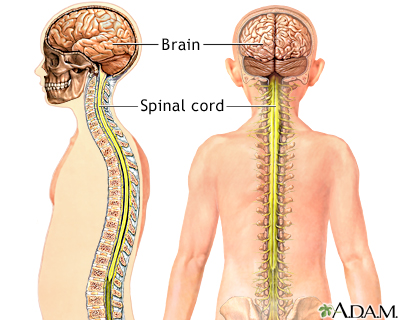

The spinal cord contains the nerves that carry messages between your brain and the rest of your body. The cord passes through your neck and back. A spinal cord injury is very serious because it can cause permanent loss of movement (paralysis), function, and sensation below the site of the injury.